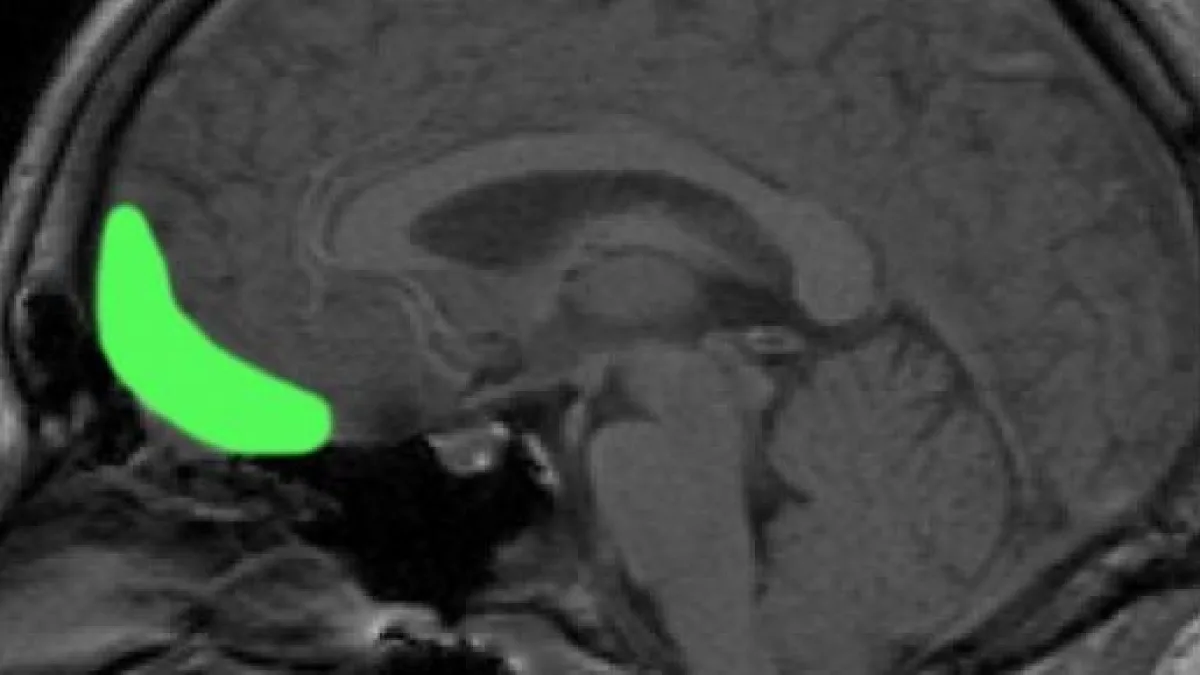

L'area di corteccia cerebrale denominata orbitofrontale laterale, che si trova grossomodo in corrispondenza dell'arcata sopracciliare, influirebbe in maniera determinante sulla scelta dei candidati da votare alle elezioni. Lo suggerisce uno studio condotto da un gruppo di ricercatori del prestigioso Montreal Neurological Institute, nella città di Montreal, in Québec, Canada.

Numerosi studi indicano che la corteccia orbitofrontale è implicata sia nel giudizio di aspetti sociali del comportamento sia nelle decisioni di carattere economico o finanziario.

"La nostra ricerca" conclude Leslie Fellows "indica che la porzione più laterale di quest'area del cervello è necessaria per porre in relazione il giudizio sociale di una persona, basato sul suo aspetto esteriore, con la decisione di votare quella persona alle elezioni".